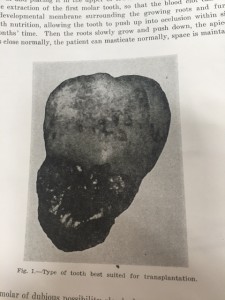

一番最初に、Fig1を見て下さい。移植にベストな歯です。って書いてあってですね、Fig1を見ると

こうゆう感じの歯がベストだそうです笑(Type Of Tooth Best Suited Transplantation)

こうゆう感じの歯がベストだそうです笑(Type Of Tooth Best Suited Transplantation)

なんか、もっと、移植に向いている何かをまとめた表みたいなのを期待していたのに・・・笑

まとめると

完全埋伏歯である。

根未完成である

傷つけない

乾燥させない

というのが大事だそうです。テクニックといいつつ、具体的な抜き方みたいなのは書いてありませんでした。